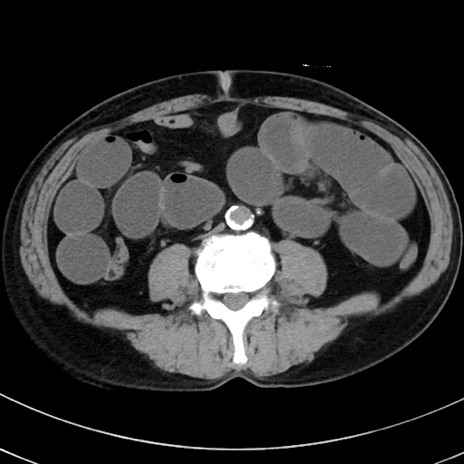

症例38(横断像)

【症例】70歳代 男性

【主訴】腹痛・嘔吐

【現病歴】昨晩より、嘔吐・腹痛あり。今朝になっても嘔吐あり。来院。

【既往歴】心臓バイパス手術、開腹胆摘、腸閉塞

【身体所見】BP 107/71mmHg、HR 116/min、腹部:平坦、軟、下腹部に軽度圧痛あり。反跳痛なし。

【データ】WBC 15100、CRP 0.32